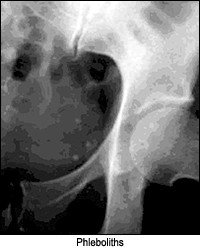

- Left lower quadrant: phleboliths, mesenteric lymph nodes, ovary, renal ureters, iliac artery.

- Right lower quadrant: appendix, phleboliths, mesenteric lymph nodes, ovary, ureters, iliac artery.

Bones are the only normal calcified structures. However, many other calcifications will be seen that have no clinical significance:

- vascular veins of the pelvis (phleboliths). Calcified thrombi within the deep veins of the pelvis should be dismissed as soft-tissue variants simulating stones of the genitourinary tract. Most of these clinically insignificant anomalies will be found lateral to the bladder walls and appear as nodular, homogenous opacities.